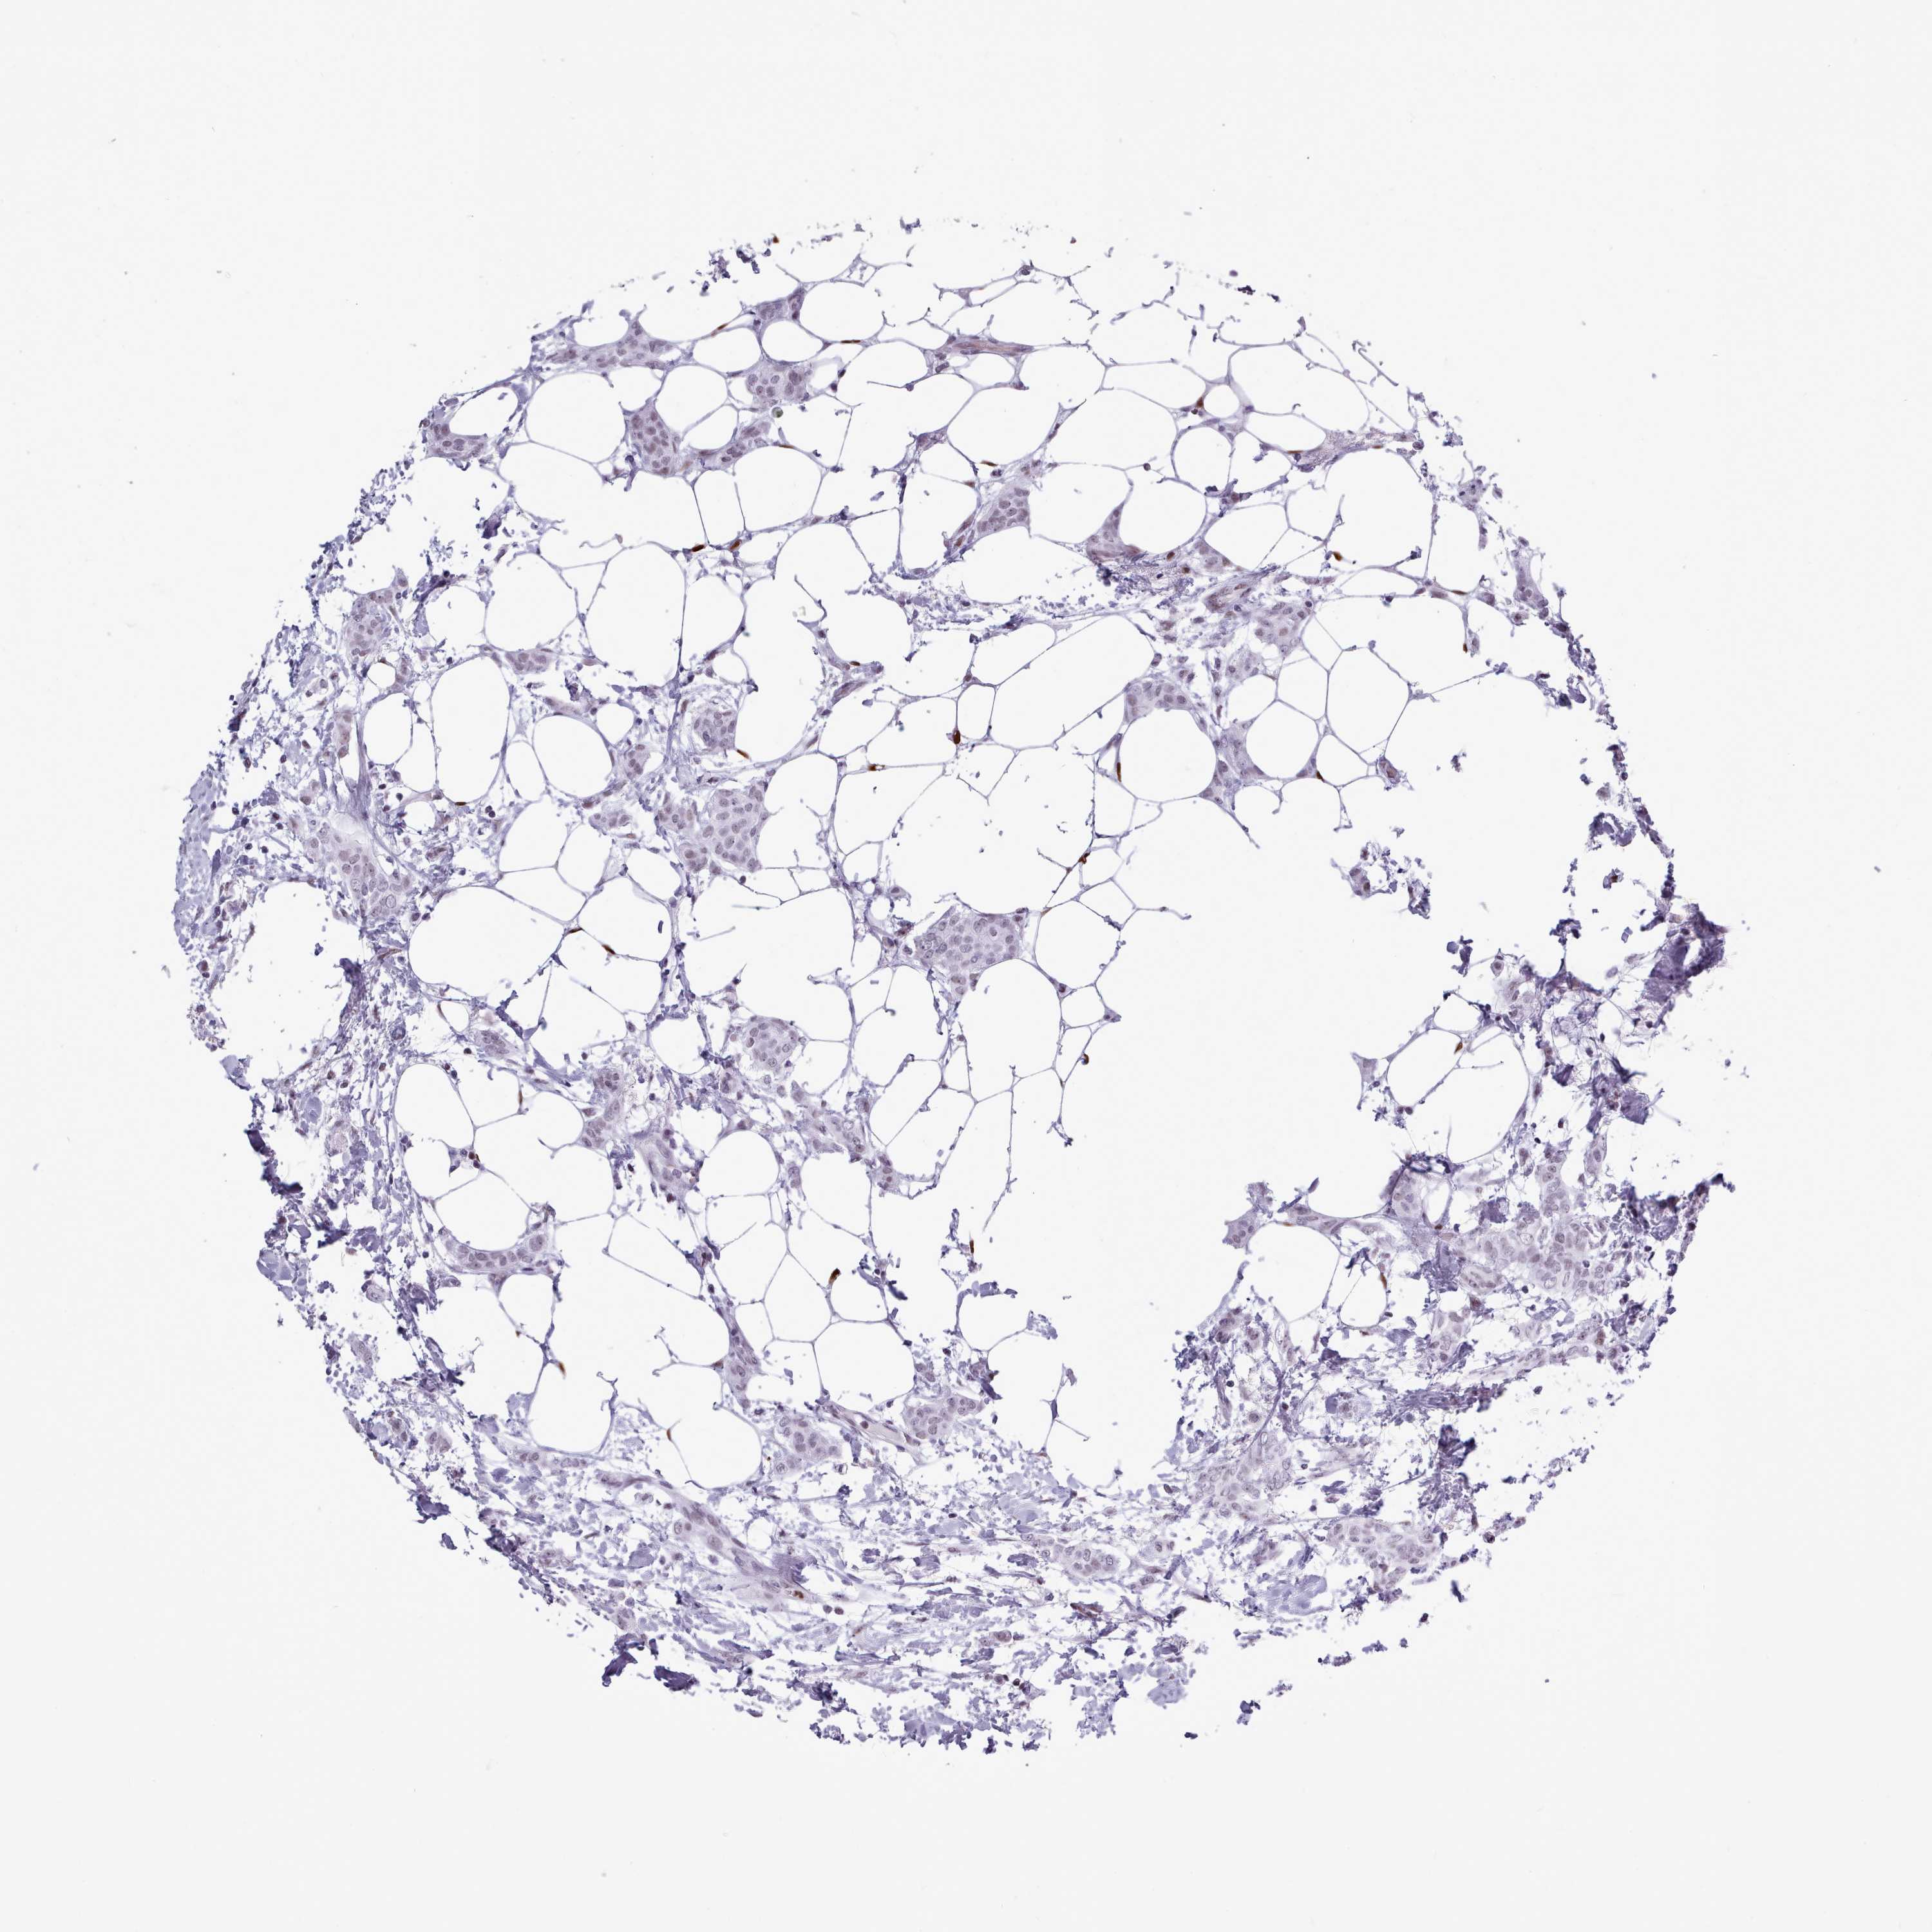

BRCA TCGA BRCA VALIDATION PROTEIN EXPRESSION

ANTIBODIES

AND

VALIDATION